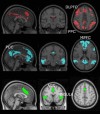

Neurofeedback concurrent with mindfulness meditation may reveal meditation effects on the brain and facilitate improved mental health outcomes. Here, we systematically reviewed electroencephalography (EEG) and functional magnetic resonance imaging (fMRI) studies of mindfulness meditation with neurofeedback (mbNF) and followed PRISMA guidelines. We identified 9 fMRI reports, consisting of 177 unique participants, and 9 EEG reports, consisting of 242 participants. Studies of fMRI focused primarily on downregulating the default-mode network (DMN). Although studies found decreases in DMN activations during neurofeedback, there is a lack of evidence for transfer effects, and the majority of studies did not employ adequate controls, for example, sham neurofeedback. Accordingly, DMN decreases may have been confounded by general task-related deactivation. EEG studies typically examined alpha, gamma, and theta frequency bands, with the most robust evidence supporting the modulation of theta band activity. Both EEG and fMRI mbNF have been implemented with high fidelity in clinical populations. However, the mental health benefits of mbNF have not been established. In general, mbNF studies would benefit from sham-controlled RCTs, as well as clear reporting (e.g., CRED-NF).

Figures